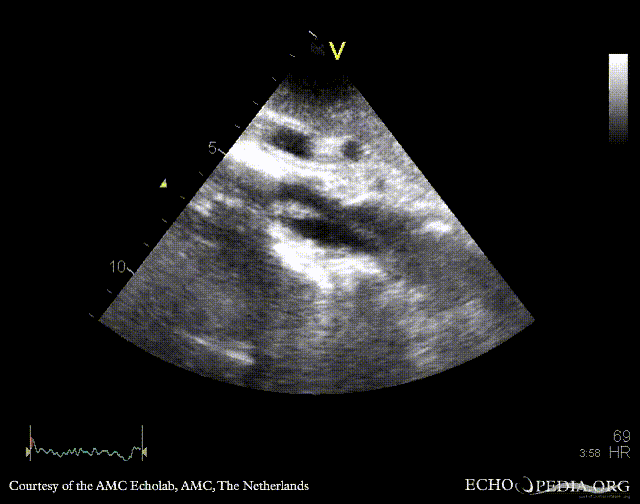

Subcostal view: mobile structure (thrombus) in abdominal aorta Subcostal view: mobile structure (thrombus) in abdominal aorta